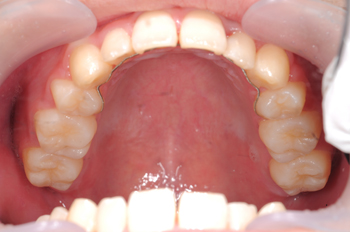

Before

顎が小さく歯が並びきらず、歯並びがデコボコになってしましっていましたので、拡大装置により、歯が並ぶスペースを作り、さらに余分な歯を取ることにより、全体のバランスを浴していきました。